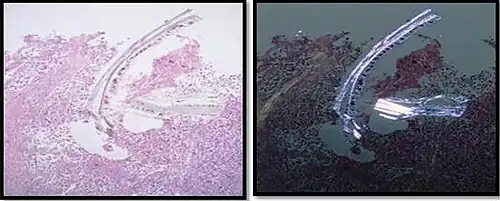

In microscopy, an artifact is an apparent structural detail that is caused by the processing of the specimen and is thus not a legitimate feature of the specimen. In light microscopy, artifacts may be produced by air bubbles trapped under the slide's cover slip.[1]

Cellulose contamination, in H&E stain and polarized light -

Cardiac muscle (bottom) with contamination from thyroid tissue (center) -